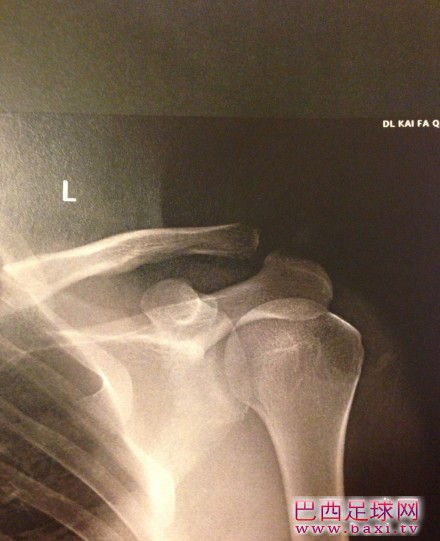

卓尔保级战前再损大将 朱挺脱臼或休战三周

本周末,中超联赛第19轮激烈角逐,武汉卓尔队0-3不敌大连阿尔滨,保级对手天津泰达2-1力克山东鲁能豪取三连胜,而长春亚泰0-0战平上海东亚拿到一分。卓尔队保级遇到窘境,屋逢连阴偏漏雨汉军又损大将,朱挺或将休战三周。